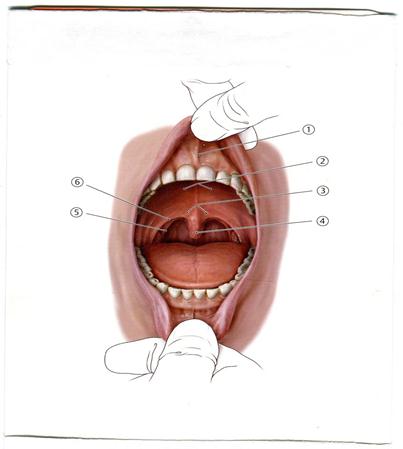

А. Таңдай бадамша безі

В. Тіл бадамша безі

С. Таңдай- тілдік доға

+D. Таңдай – жұтқыншақтық доға

Е. Шекаралық жүлге

A+++++. Жоғарғы жүгеншік

B. Таңдай- тілдік доға

C. Таңдай –жұтқыншақтық

D.Тілшік

E. Қатты таңдай

84. Тістерді жұлу кезінде, оларды жансыздандыруымен бірге тілдің шырышты қабығының талтильді сезімталдығы жойылады. Тілдің шырышты қабығының қандай бүрлерінің қызметі істен шығуы мүмкін?

А++. Жіпше тәрізді

B. Жалпақ

C. Конус тәрізді

D. Саңырауқұлақ тәрізді

Е. Тіласты

86. Тістерді пломбылау кезінде, ауыз қуысындағы сілекейдің бөлінуін азайту мақсатында, құлақ маңы безінің түтігін жабу үшін, мақта тампонын қай тістің деңгейінде қоюы керек?

А. 1- ші жоғарғы кіші азу тістің

B. 1- ші төменгі кіші азу тістің

C. ++2 - ші жоғарғы үлкен азу тістің

D. 2 - ші төменгі үлкен азу тістің

E. 3- ші төменгі үлкен азу тістің